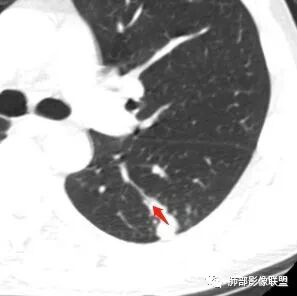

男性,胸疼,左肺下叶背段结节,边缘光滑,有平直收缩,轻度延迟强化?胸膜肥厚,有轻度胸膜牵拉,周围有卫星灶,考虑炎性病变,结核,隐球可能性大。鉴别腺癌。

左肺下叶背段结节,边缘较光整,平直,近端支气管未见明确截断征象,沿支气管走行,临近胸膜局限性增厚,增强目测未见明确强化,周围见稀疏小树芽分布,整体考虑良性病变,结核放前考虑。

左肺下叶背段结节,边缘光滑,有平直收缩,强化不明显,胸膜肥厚,有轻度胸膜牵拉,周围有卫星灶,考虑感染性病变,结核首选。

左肺下叶背段近胸膜下结节,部分边缘平直并可见卫星灶,增强后强化不明显,首先考虑结核。